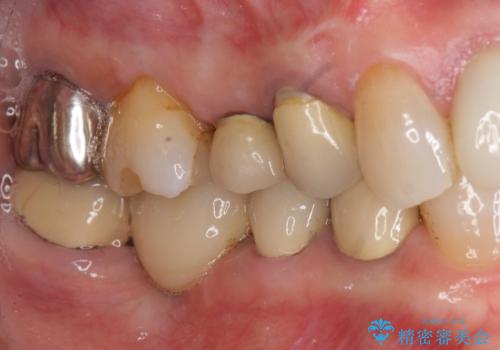

[ インプラント治療 ]失った奥歯を回復したい